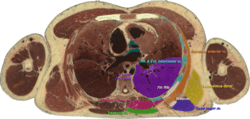

![]() Cross section #1428 of the Visible Human Male showing the structures of the triangle of auscultation, created in the VH Dissector | |

The superficial floor of the triangle is formed by the lateral portion of the erector spinae muscles. Deep to these muscles are the osseous portions of the 6th and 7th ribs and the internal and external intercostal muscles.